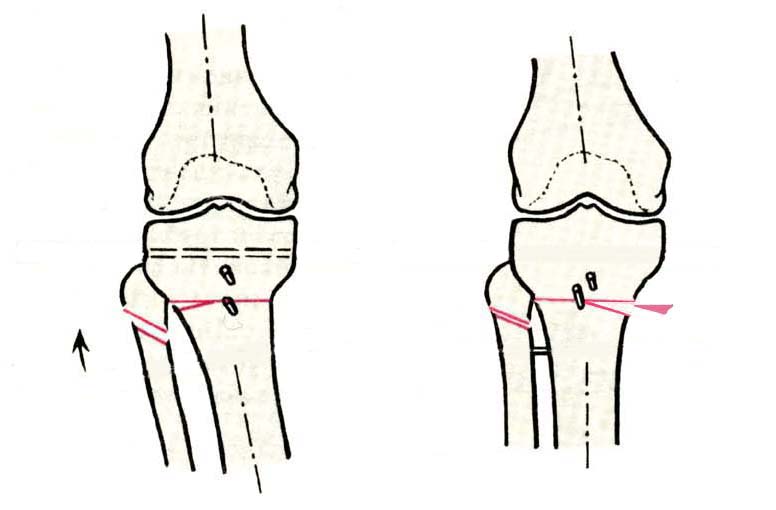

Дополнительными методами диагностики являлось измерение внутрикостного давления в зоне гипернагрузки и радионуклидные исследования нуклидами технеция. Применялись различные варианты остеотомий на различных сегментах. Для коррекции варусной-торсионной деформации:

высокие плюс, минус остеотомии большеберцовой кости,косая остеотомия малоберцовой. Для коррекции вальгусной деформации применялась плюс, минус надмыщелковая остеотомия бедренной кости. Фиксацию при высокой подмыщелковой остеотомии производили уникальной клинковой пластиной и тяговыми кортикальными винтами. Угол коррекции выставлялся

специальным угломером и направителем.

Плюс, минус - это при одной операции? В смысле, и иссекали небольшой клин, и оставляли открытый с другой стороны?

>Плюс, минус - это при одной операции? В смысле, и иссекали небольшой

>клин, и оставляли открытый с другой стороны?

В зависимости от баланса связок, комбинировали (+-)остеотомии или производили полную

минус или плюс остеотомию